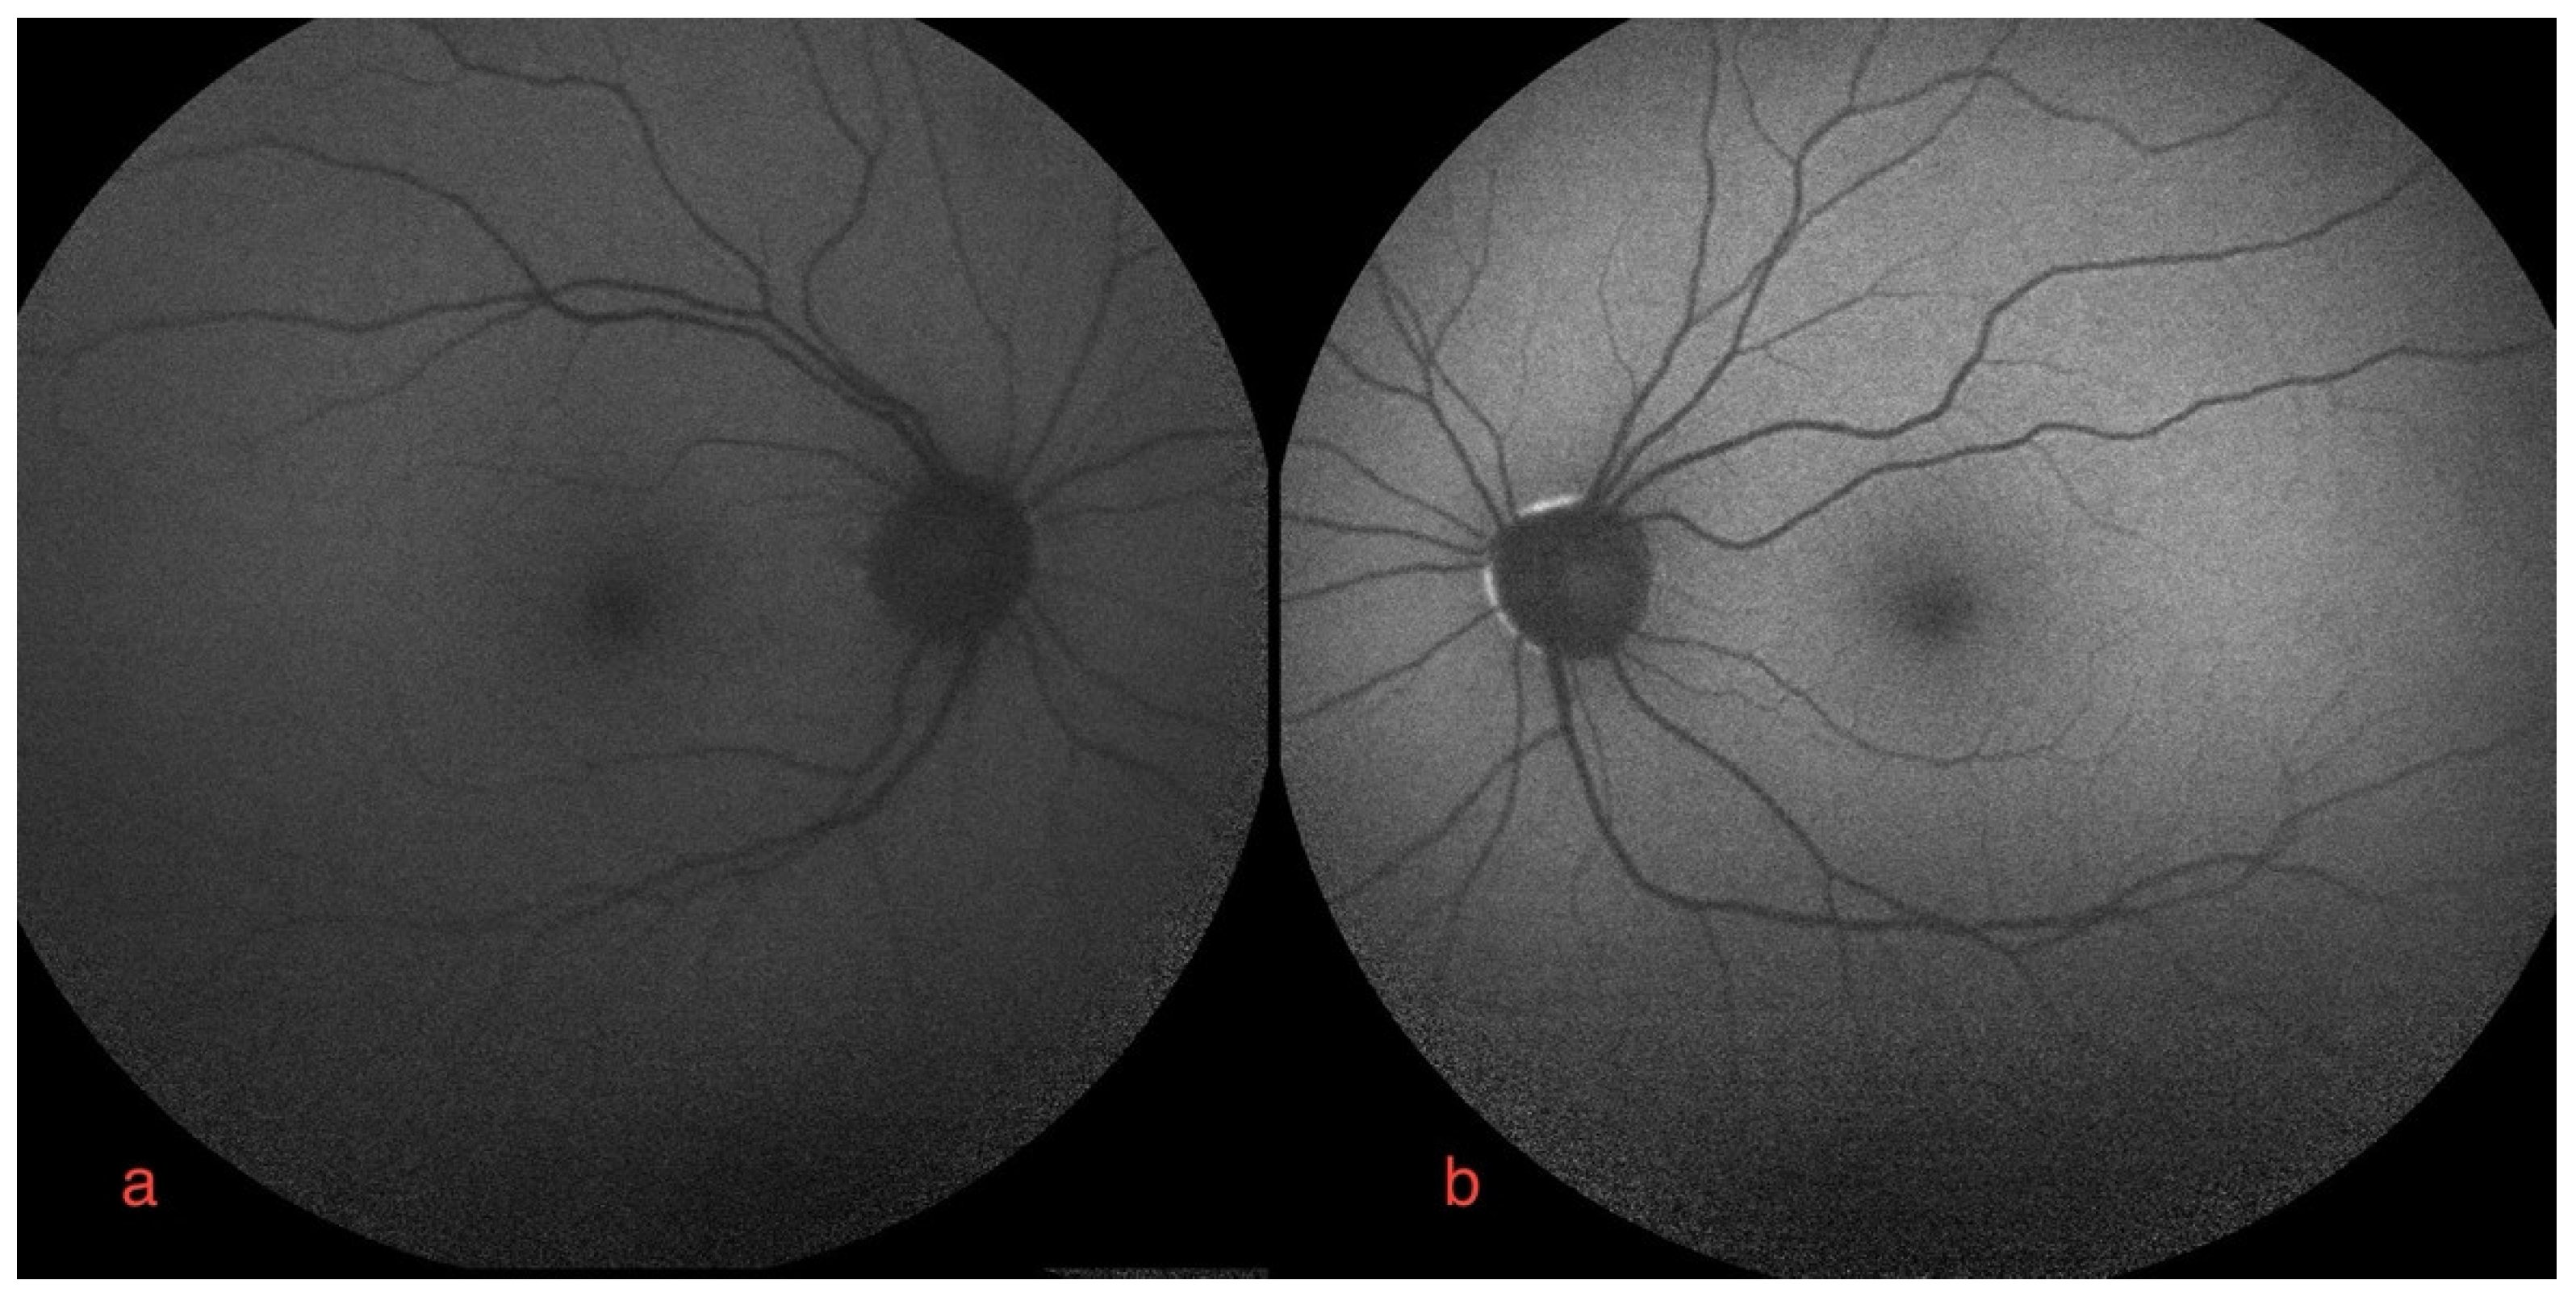

Figure 3.

Autofluorescence imaging of right (a) and left eye (b).

Bilateral FGFRARshows normal autofluorescence imagine.